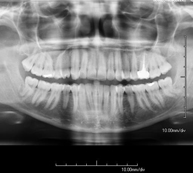

- TMJ X-ray (Temporomandibular Joint)

This technique uses X-ray rendered imaging for examining the temporomandibular joint. Indicated for: trauma, chewing pain, chewing noise, limited mouth opening.